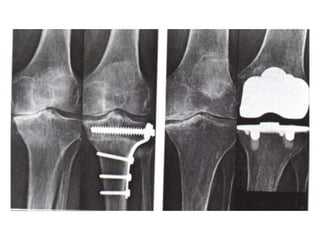

INDICATIONS OF SURGICAL

INTERVENTION

• Severe joint pain,

resistant to conservative treatment

methods

• Limitation of daily living activities

• Deformity, angular deviations, instability

INVASIVE METHODS

Osteotomy

Joint replacement

INDICATIONS OF SURGICAL INTERVENTION •Severe joint pain, resistant to conservative treatment methods • Limitation of daily living activities • Deformity, angular deviations, instability

INVASIVE METHODS • Jointlavage • Arthroscopy • Cartilage grefting- genetic engineering • Surgery Osteotomy Joint replacement